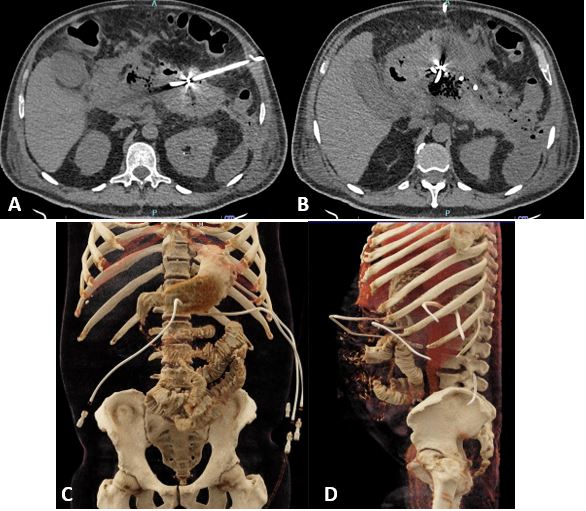

El cultivo de las colecciones informó Escherichia coli multisensible, por lo cual se ajustó el tratamiento a piperacilina- tazobactam. Tras 5 semanas desde la colocación de los catéteres evolucionó satisfactoriamente, con escasa secreción, por lo que se realizó otra TC (Fig. 3) que describe catéteres dirigidos a colecciones en la transcavidad de los epiplones, retrogástrico y pararrenal anterior, con aisladas imágenes de densidad aérea en menor cuantía en relación con el estudio previo, una disminución de más del 80% de las colecciones. Entonces se decidió el retiro de los catéteres, se mantuvo únicamente el transgástrico, se ordenó alta médica con ciprofloxacina durante 7 días más y control ambulatorio para retiro de catéter, lo cual se cumplió tras completar 45 días desde su colocación.

Figura 3. TC de abdomen simple y contrastado control: catéteres dirigidos a colecciones en la transcavidad de los epiplones, retrogástrico y pararrenal anterior, con aisladas imágenes de densidad aérea en menor cuantía en relación con el estudio previo.